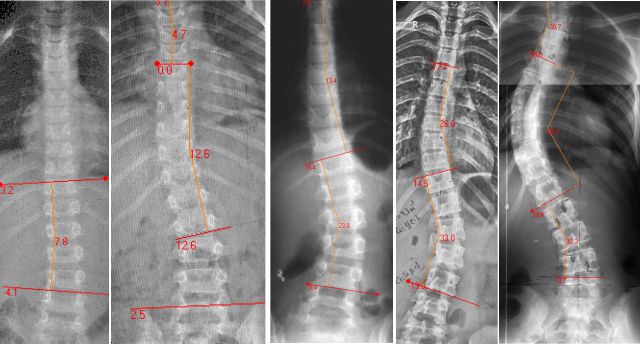

Медицинские снимки: рентген позвоночника сбоку